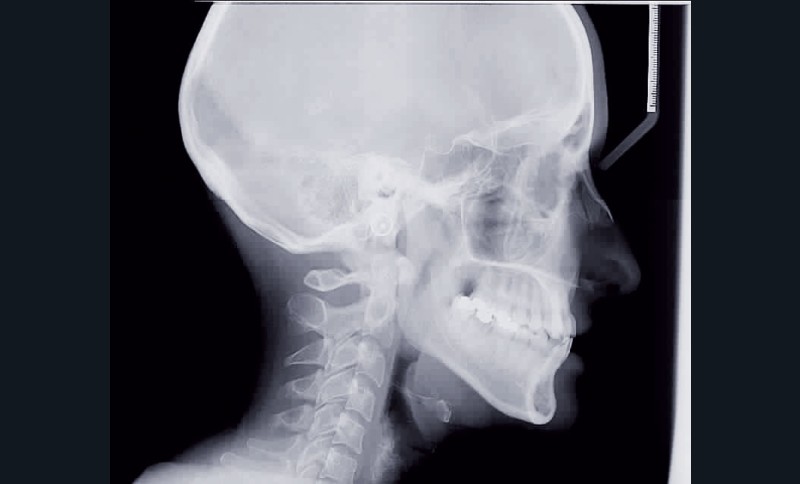

Le sourire est inesthétique (fig. 3) et de profil il existe une rétrochéilie supérieure (fig. 2).